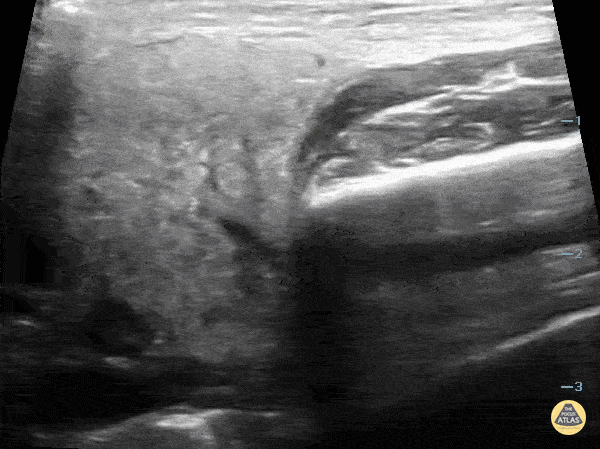

6 yo with right sided facial swelling. No fever. POCUS shows parotitis without stone. Contributor: Paul Khalil, MD Nicklaus Children's Hospital @khalil3paul